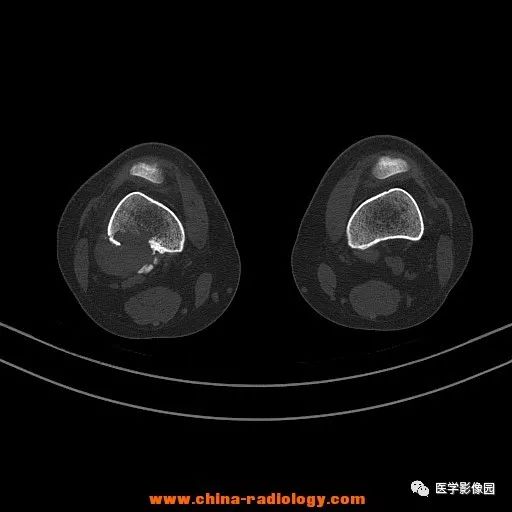

患者女性,29岁,右膝关节痛疼3月余,局部无红肿。

影像学表现:右股骨远端外后方可见局限性骨质破坏及软组织肿块,边界清楚。